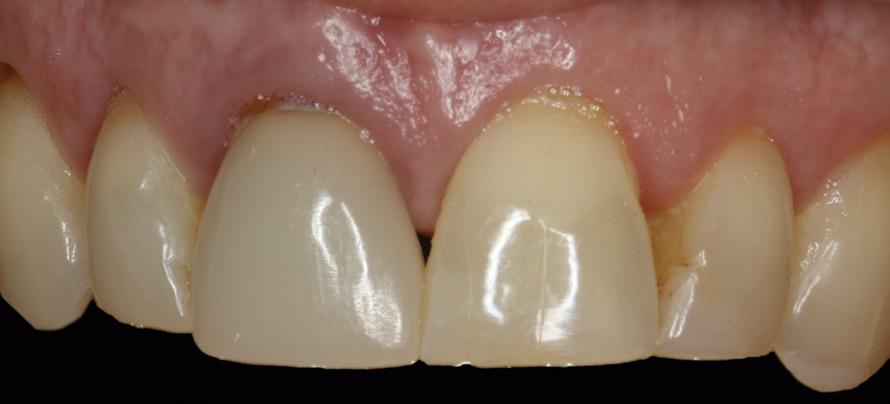

The patient was postoperatively evaluated at 1-, 2-, 4-, 8-, and 12-week recall appointments. The sutures were removed at the 2-week appointment, and the patient was instructed to rinse twice daily and avoid brushing the anterior maxilla. Prior to provisionalization of the implant, the site was allowed to heal for 6 months, during which time the patient was temporized with another Maryland bridge. At the 6-month recall appointment, full mouth periodontal maintenance was completed, and an implant-retained acrylic provisional restoration was placed (Figure 23 through Figure 25). An acrylic provisional restoration allows for soft-tissue attachment while preventing apical migration of the gingival margin. After a 3-month provisionalization period, the final prosthesis was delivered (Figure 26 through Figure 29), and the patient was scheduled for ongoing 3-month recall appointments for periodontal maintenance.

(26.) Facial and occlusal views of the soft-tissue contour achieved after 3 months of provisionalization. The tissue is thick with a harmonious gingival contour and zenith position.

Figure 26

(27.) Facial and occlusal views of the soft-tissue contour achieved after 3 months of provisionalization. The tissue is thick with a harmonious gingival contour and zenith position.

Figure 27

(28.) Facial view and radiograph of the final implant-supported crown.

Figure 28

(29.) Facial view and radiograph of the final implant-supported crown.

Figure 29